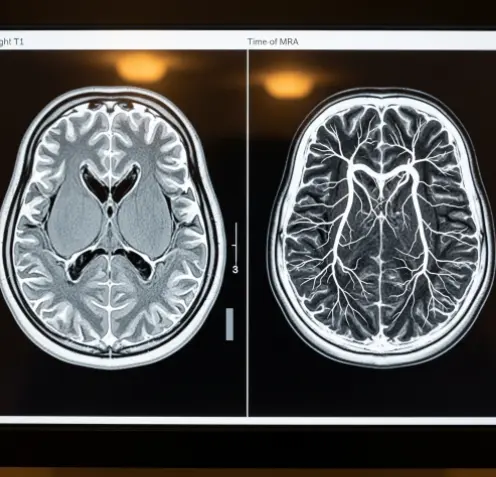

- 뇌 MRI (자기공명영상): 집의 '내부 인테리어'를 보는 검사입니다.

- 방 구조는 잘 되어 있는지, 벽에 곰팡이는 없는지, 가구가 부서지진 않았는지를 봅니다. 즉, 뇌의 '실질적인 살(조직)' 모양을 찍습니다.

- 뇌 MRA (자기공명혈관조영술): 집 벽 속에 숨겨진 '수도 배관(보일러 배관)'만 따로 보는 검사입니다.

- 물이 흐르는 파이프가 꽉 막히진 않았는지, 혹은 파이프가 낡아서 꽈리처럼 부풀어 오르진 않았는지를 봅니다. 즉, 뇌의 '혈관'만 집중해서 찍습니다.

MRI(Magnetic Resonance Imaging)는 강력한 자석의 힘을 이용해 뇌의 단면을 사진처럼 찍어내는 검사입니다.

MRA(Magnetic Resonance Angiography)에서 'A'는 Angiography, 즉 혈관 조영술을 뜻합니다. 뇌 조직은 투명하게 처리하고 오직 '혈관의 길'만 입체적으로 보여줍니다.